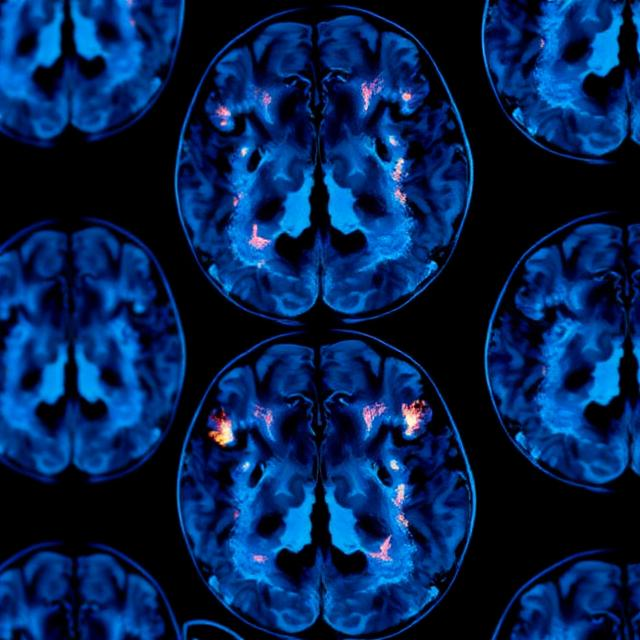

The ALTITUDE-AD trial is investigating sabirnetug, a monoclonal antibody with high selectivity for A-beta oligomers, which are believed to play a pivotal role in the development and progression of Alzheimer's disease. The study has shown positive effects on phospho-tau-181 and neurogranin levels in cerebrospinal fluid (CSF) after just three doses at the final three-month time point. These biomarkers have gained acceptance as diagnostic and clinical markers of disease, providing a competitive edge for Acumen's therapy.